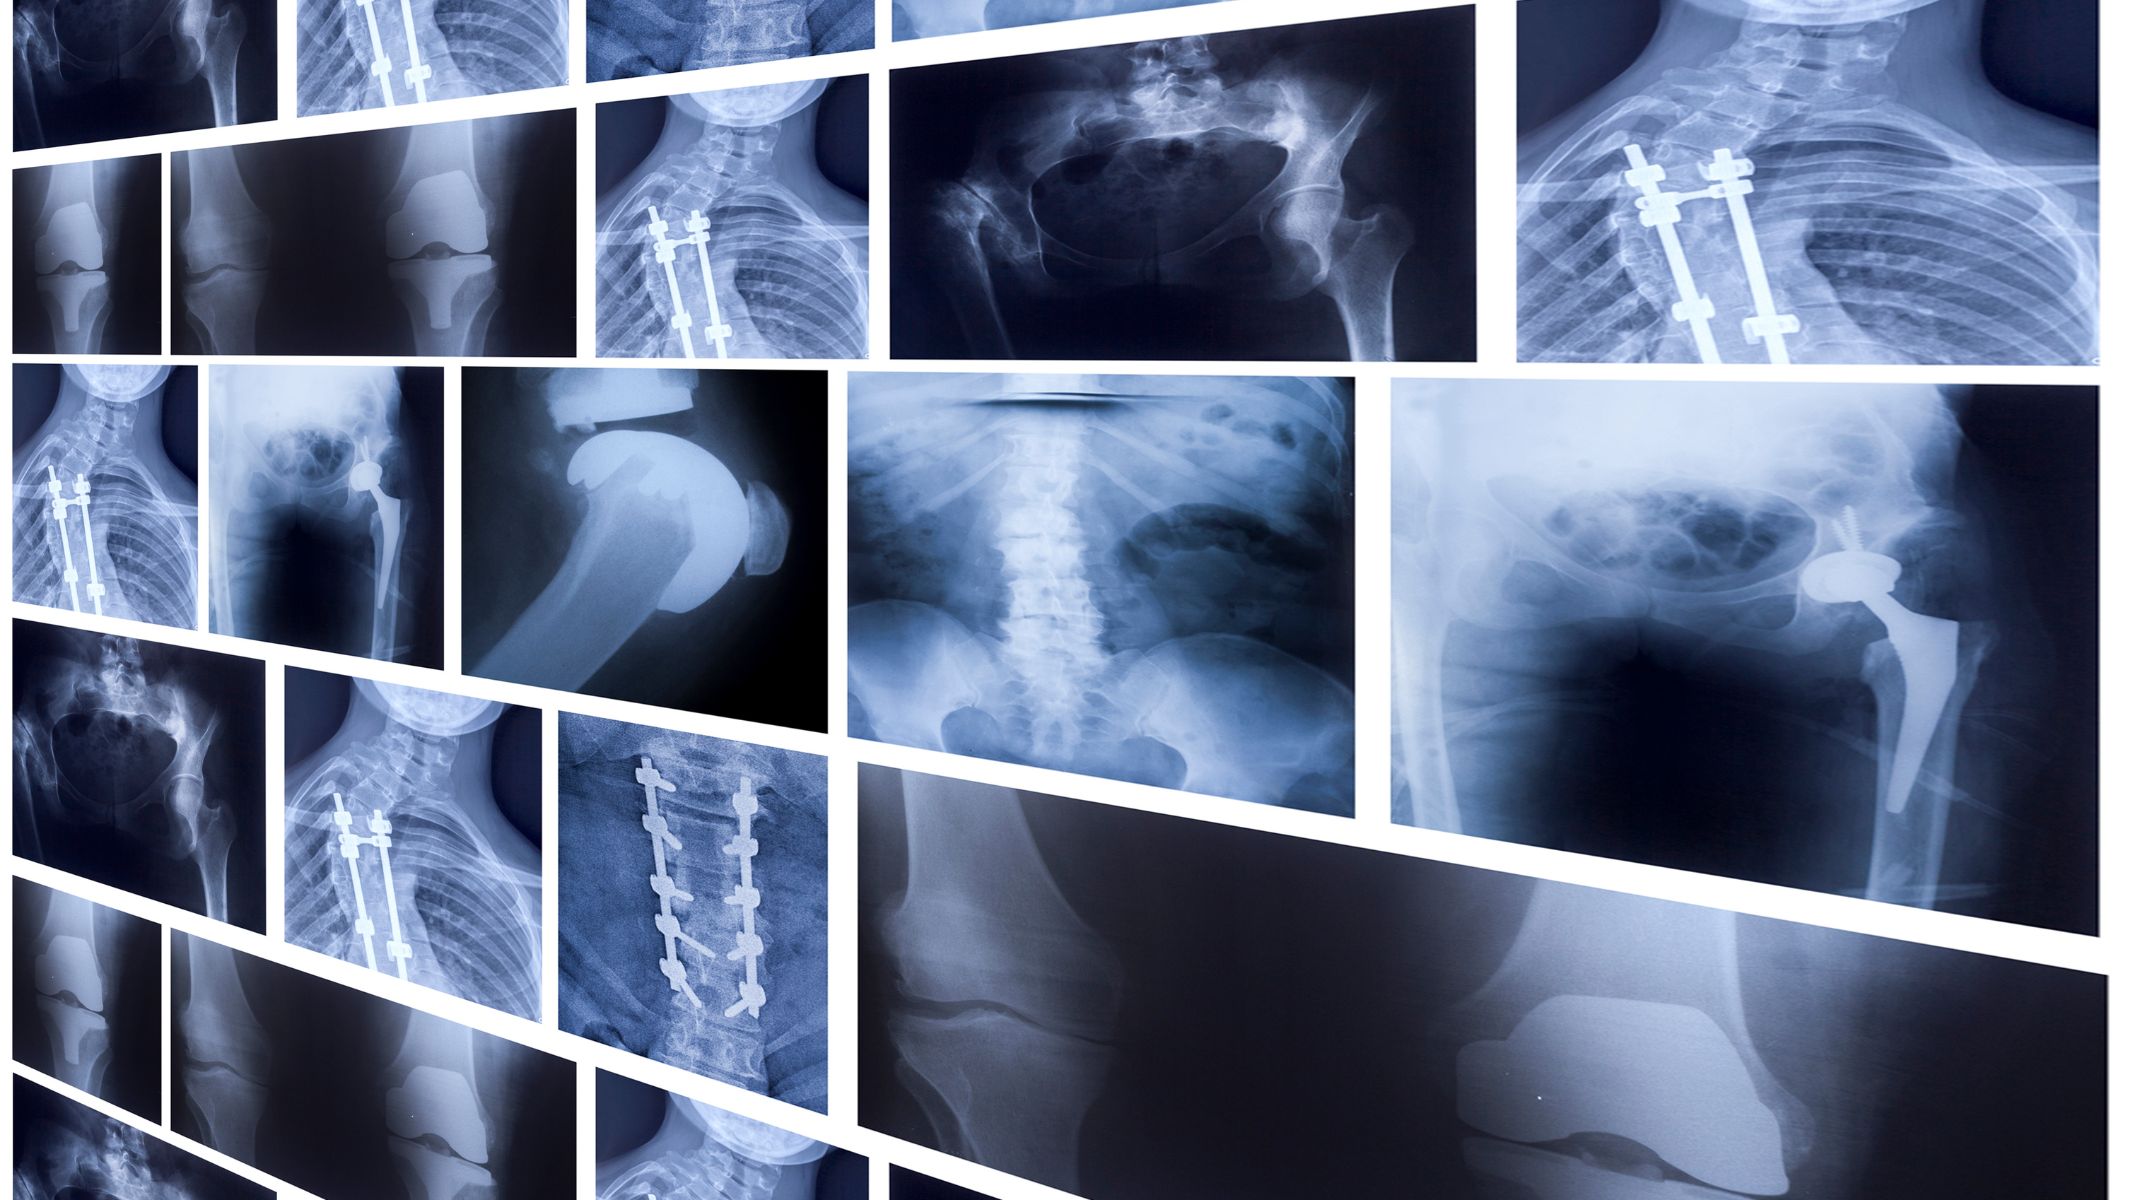

Chụp X-quang

X-quang là kỹ thuật đầu tiên thường được thực hiện khi bác sĩ nghi ngờ có vấn đề tại xương. Hình ảnh X-quang giúp phát hiện những biến đổi trong cấu trúc xương như mất chất xương, xương bị mỏng hoặc xuất hiện vùng đặc bất thường. Đây là xét nghiệm đơn giản, nhanh chóng và giúp định hướng các bước tiếp theo trong quá trình chẩn đoán.